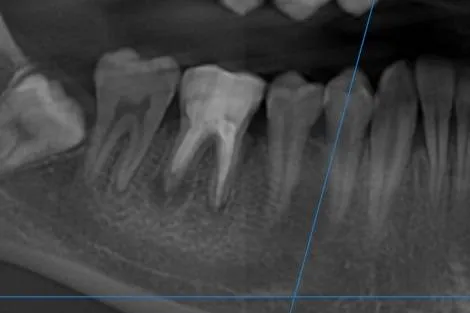

Tratament endodontic molar inferior cu elongare coronară și reconstrucție corono-radiculară Detalii caz